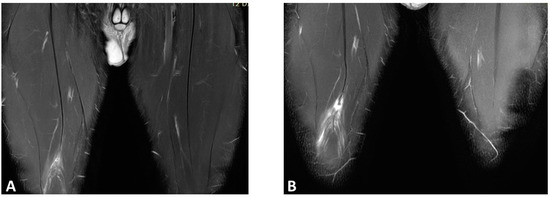

- Isern-Kebschull, J.; Pedret, C.; Mechó, S.; Pruna, R.; Alomar, X.; Yanguas, X.; Valle, X.; Kassarjian, A.; Martínez, J.; Tomas, X.; et al. MRI Findings Prior to Return to Play as Predictors of Reinjury in Professional Athletes: A Novel Decision-Making Tool. Insights Imaging 2022, 13, 203. [Google Scholar] [CrossRef] [PubMed]